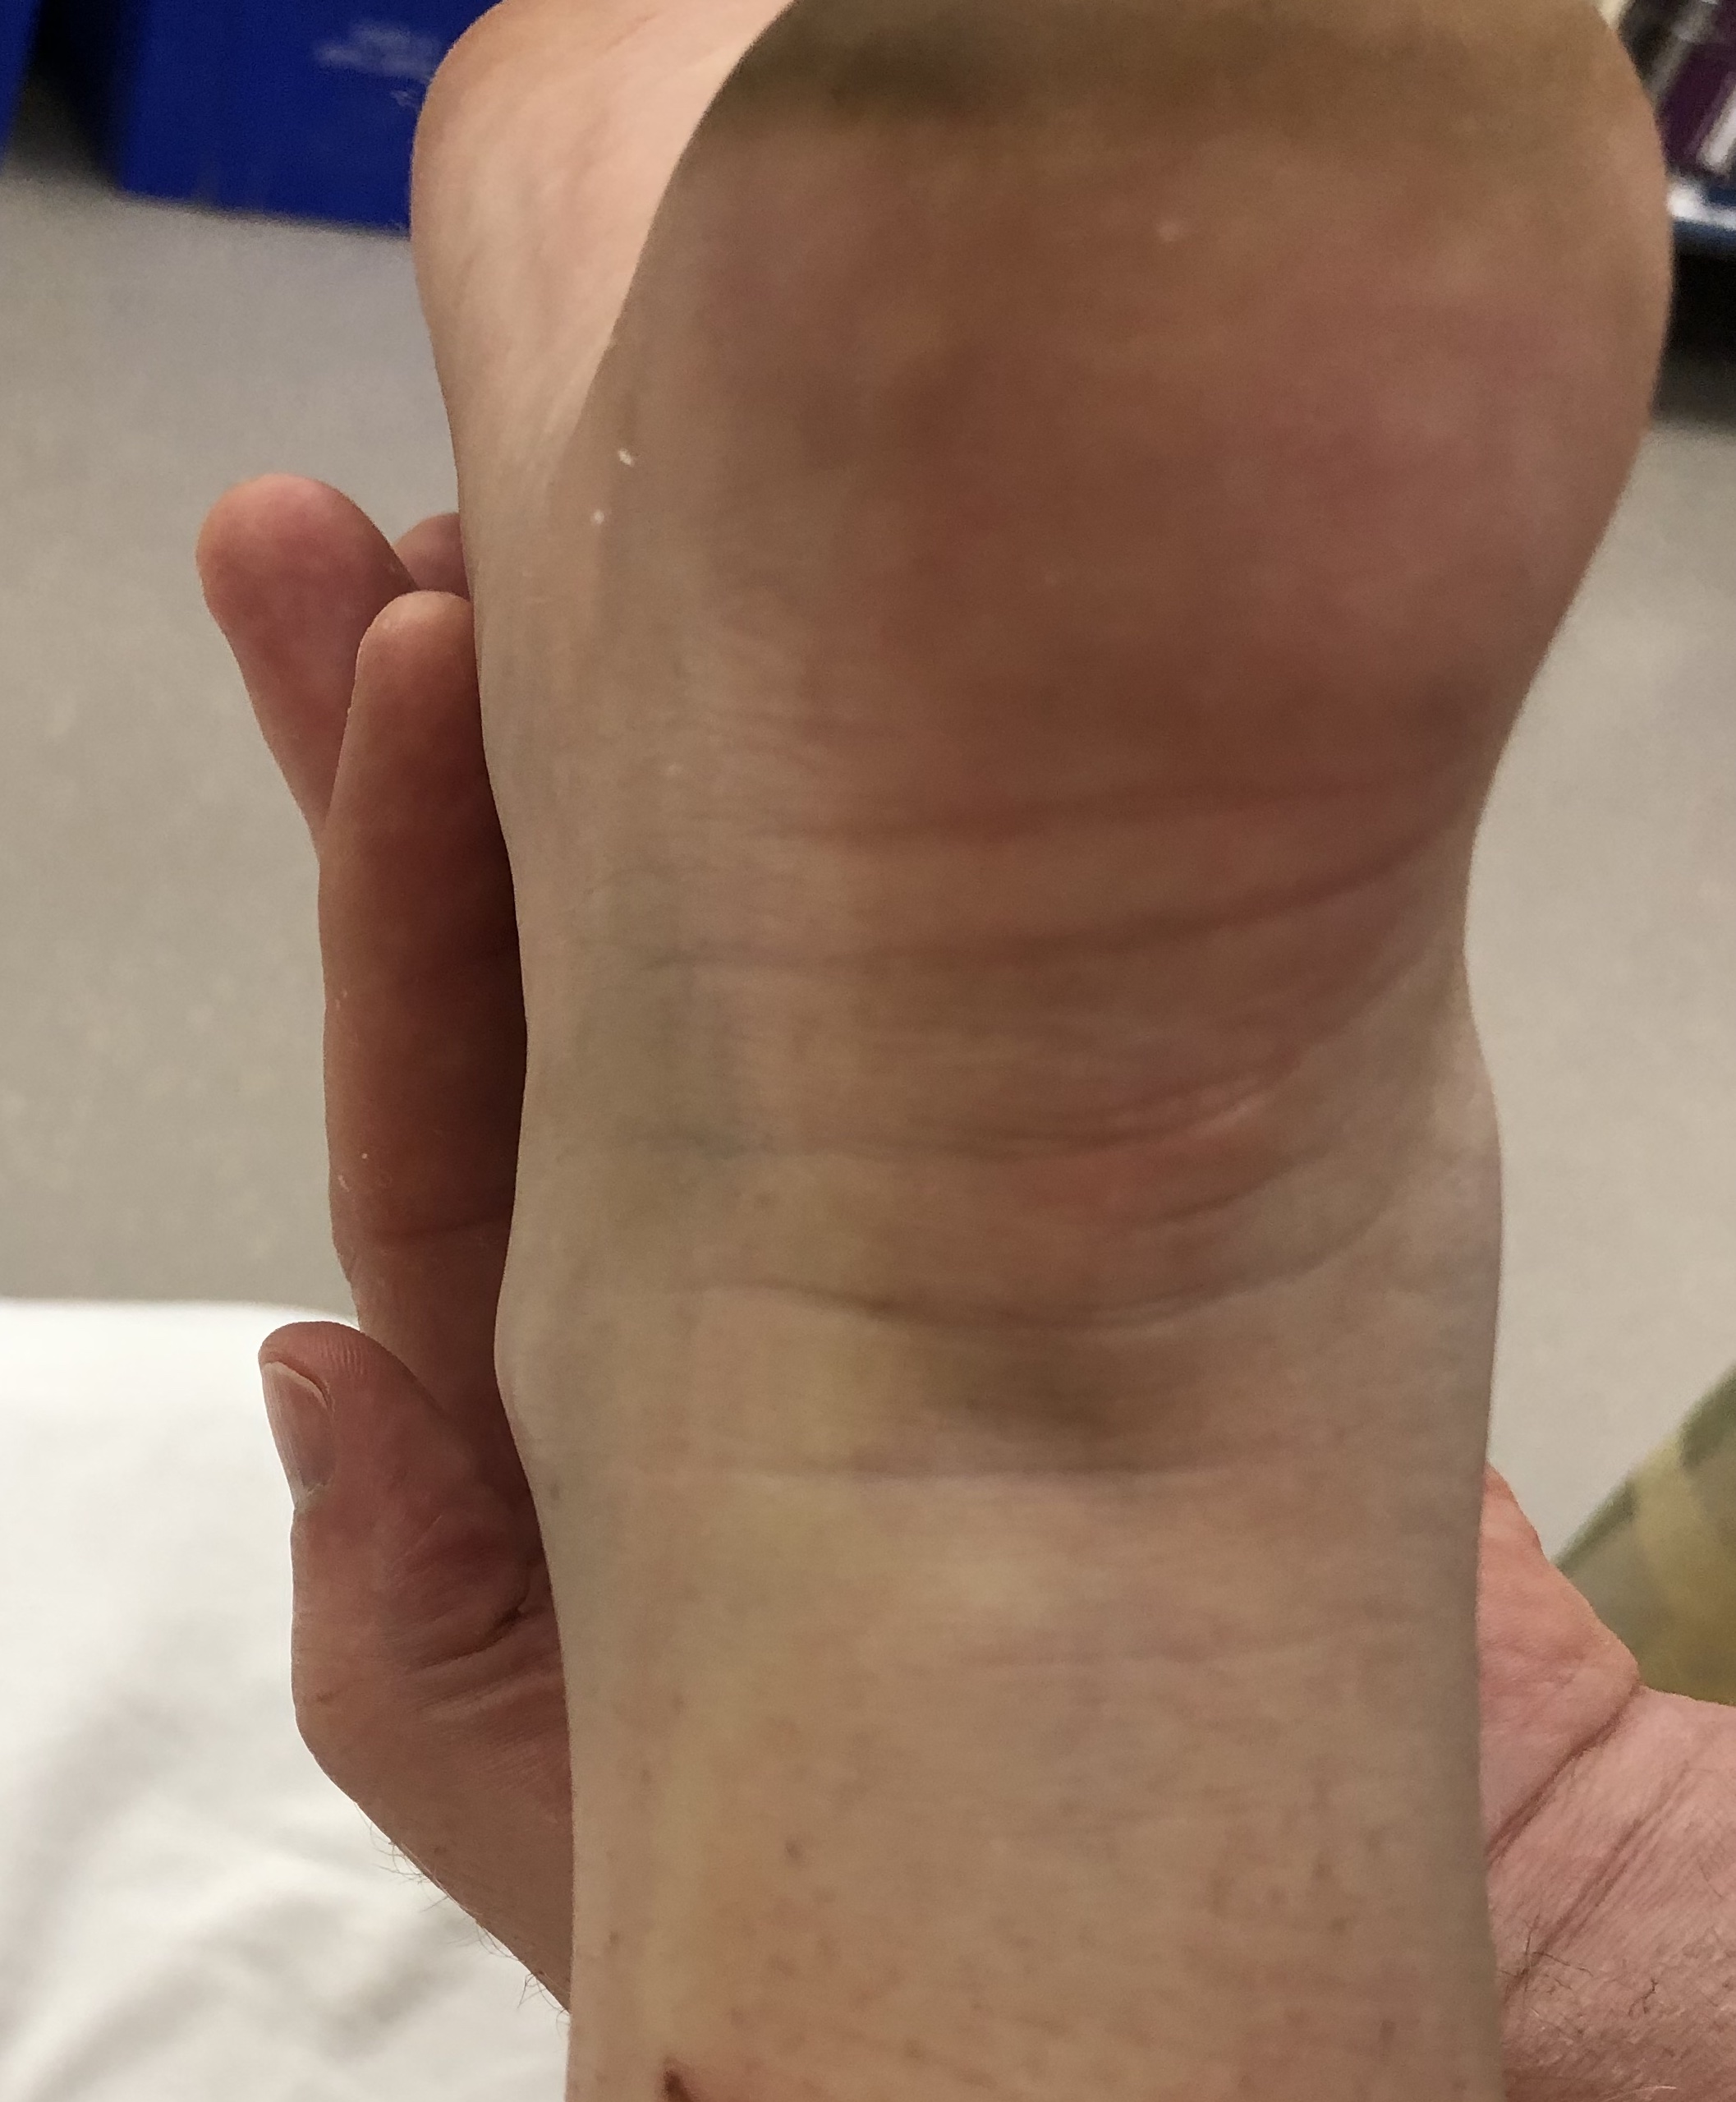

Acute tear

Significant swelling

Visible / palpable gap